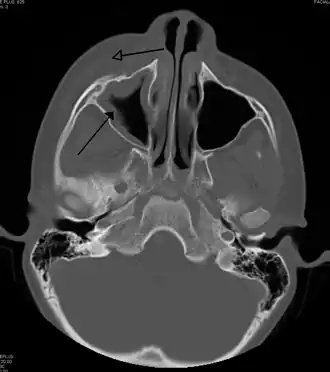

Периорбитальный целлюлит, вызванный стоматологической инфекцией (которая также приводит к верхнечелюстному синуситу))

Периорбитальный целлюлит необходимо дифференцировать от орбитального целлюлита, который является чрезвычайной ситуацией и требует внутривенного введения (IV) антибиотиков. В отличие от орбитального целлюлита, у пациентов с периорбитальным целлюлитом отсутствуют выпуклые глаза (экзофтальм), ограниченное движение глаз (офтальмоплегия), боль при движении глаз, или потеря зрения. Если какой-либо из этих признаков присутствует, надо полагать, что пациент имеет орбитальный целлюлит и начать лечение IV антибиотиками. КТ-сканирование может быть сделано, чтобы очертить расширение инфекции.